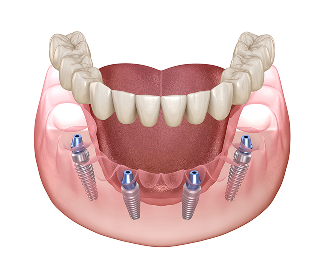

All-4-U 임플란트는 기존의 ‘All-on-X’ 개념에

서울하늘에치과만의 ‘UV 임플란트’와

‘100% 디지털 시스템’을 더해 탄생한,

새로운 개념의 혁신적인 치료이자 환자 맞춤형 솔루션입니다.

All-4-U 임플란트의 장점

• · 틀니와 달리 완전 고정식 구조로 탈착이 불필요

• · 전체 임플란트보다 적은 개수로 비용과 시간이 크게 절약

• · 뼈이식을 최소화하여 수술 부담과 통증을 낮추고, 회복 기간 단축